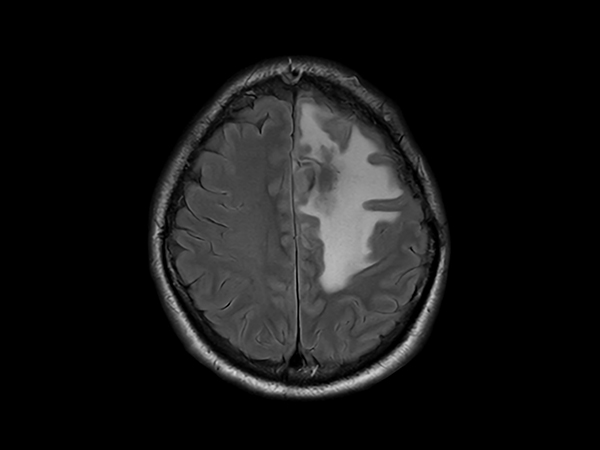

SmartSpeed Precise imaging for brain with glioblastoma

Kyushu University Hospital Japan